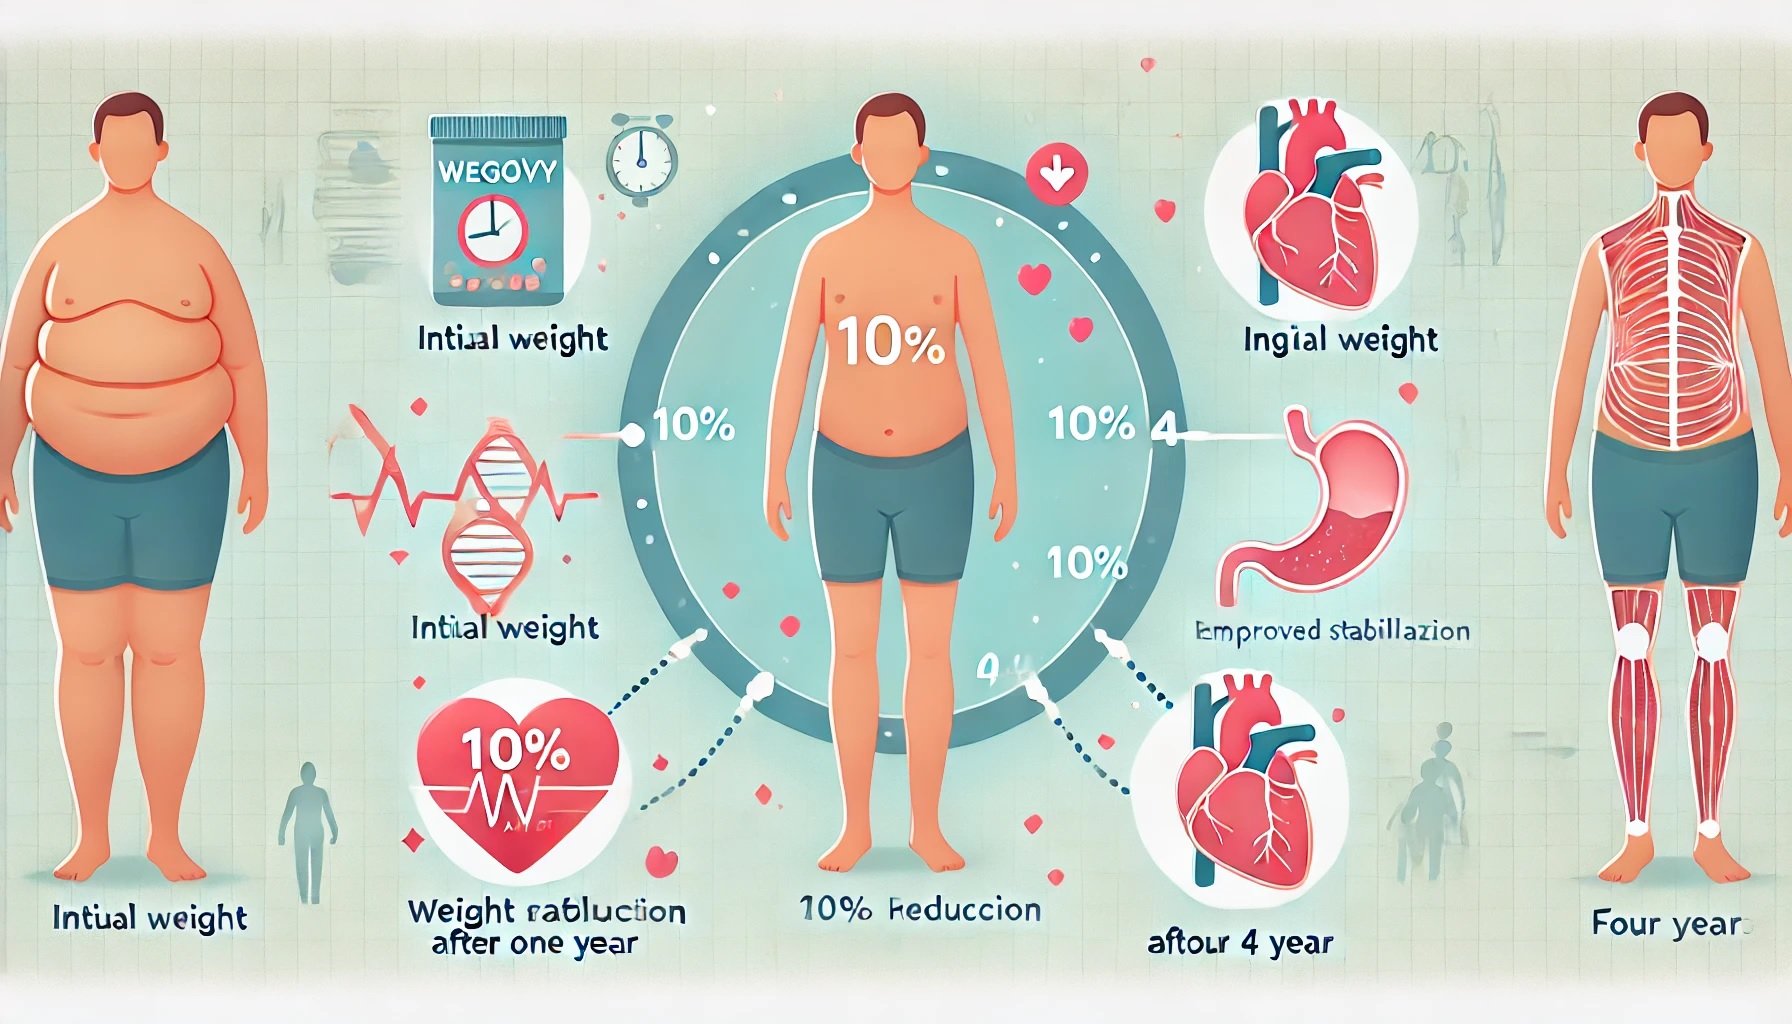

Wegovy Access Expands: Novo Nordisk Partners with Telehealth Giants

Wegovy Access Expands Through Telehealth Partnerships Novo Nordisk is significantly expanding acces...